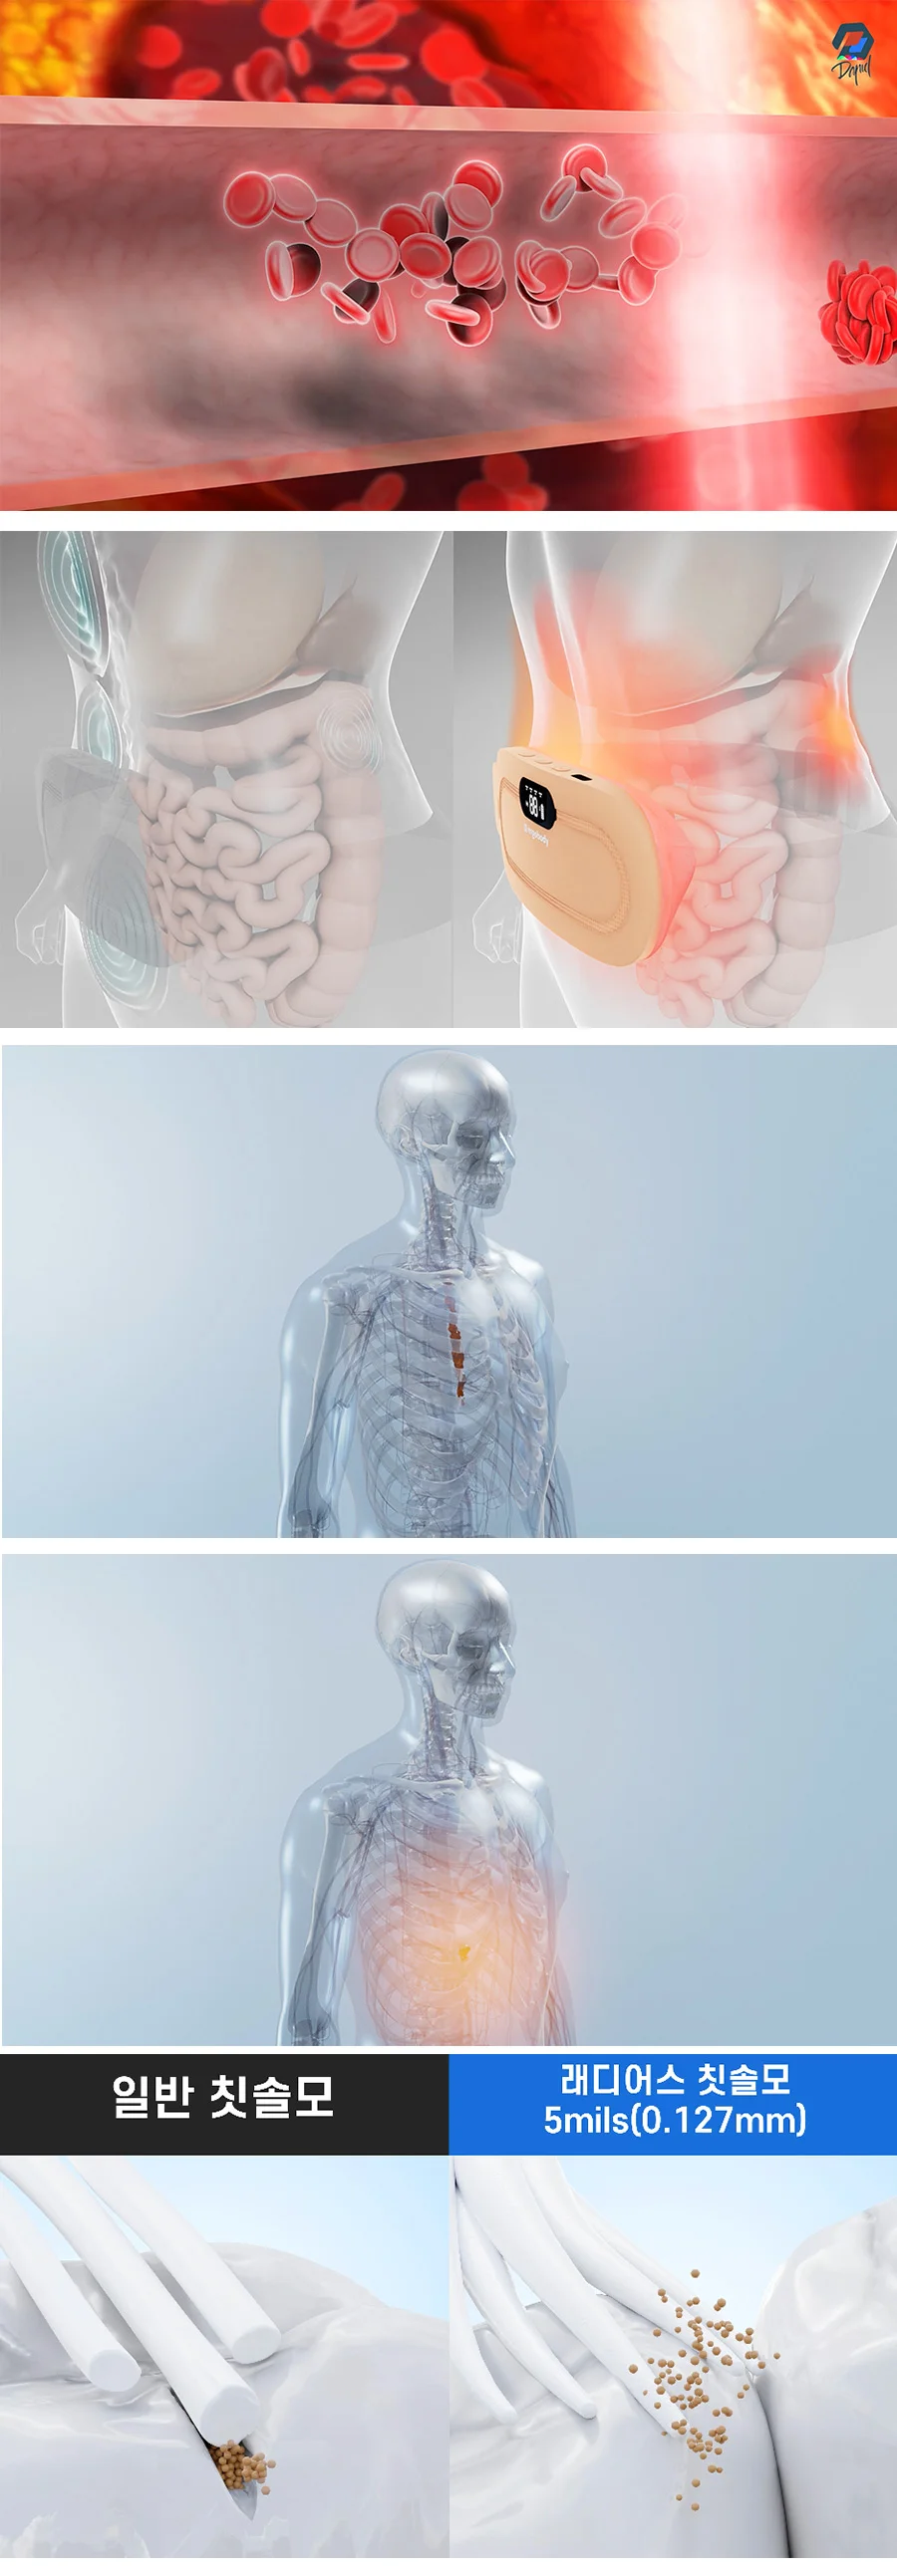

의학 관련 : 의료 효과,신체 해부학

의료, 의학 , 의료기기 시뮬레이션 제작

ex) 피부에 화장품이 스며드는 장면 ( 세포, 입자 등)

ex) 신체조직 혹은 신체안에서 변화&반응하는 시뮬레이션

ex) 의료기기의 원리

ex) 의료기기 홍보영상 등